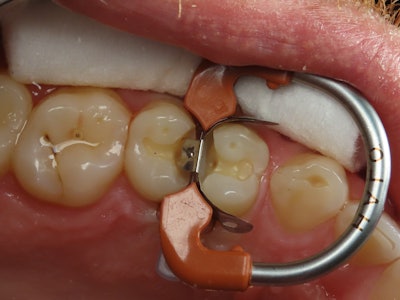

As part of my standard class II protocol, after the bond has been thinned out, I will place a very small layer of RE-GEN Flowable (Vista Apex) at the base of the proximal box and co-cure it and the bond together (see Figure 5).

Figure 5: Restoring adjacent Lesions with the Halo Matrix, which show adequate contour and great sealing at the gingival margin.

The prepared site is rebuilt using a combination of everX Flow (GC) and Exquisite Restoration nanofill composite (Vista Apex) in multiple layers. After final curing, the NiTi ring is removed, and the edges are cured from both sides before final removal of the separating wedge and matrix band.